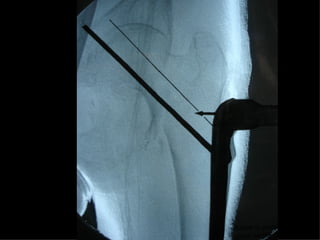

Accurata riduzione percutanea della frattura

Precise vie di accesso